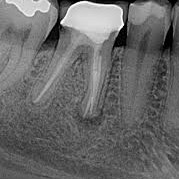

La endodoncia en dientes anteriores es un tratamiento dental que se realiza para eliminar la pulpa infectada o dañada...